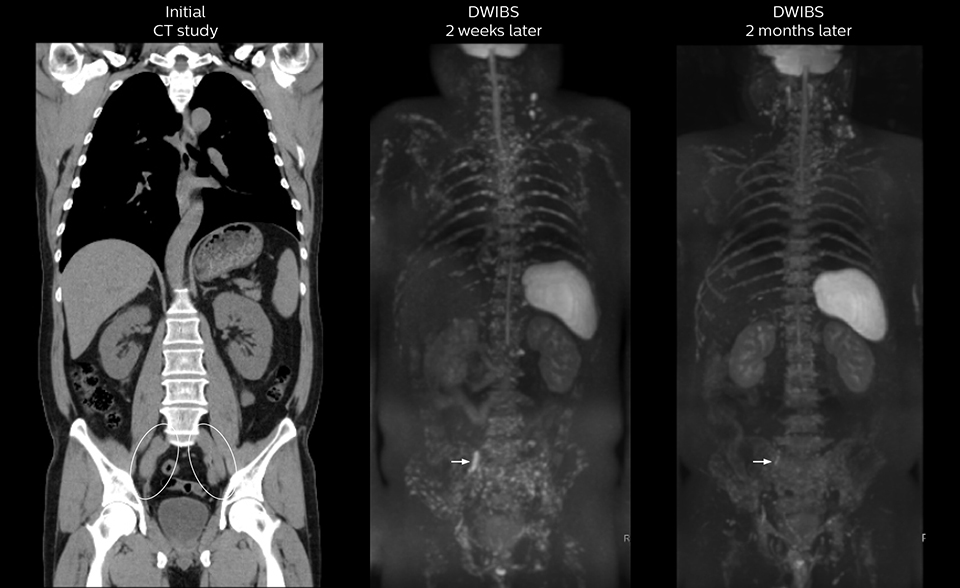

After implementing the improved whole body protocol, the radiology team initially did not see a large increase in referrals, although Dr. Nobusawa saw clinical cases where the DWIBS images provided him valuable information for diagnosis. This is why Dr. Nobusawa and Mr. Naka started to actively educate referring physicians about the value of whole body DWIBS. They organized several presentations for physicians in the hospital, where they explained how DWIBS can be of value in oncology patients. The information it provides can be useful for physicians when staging cancer, as well as when determining or adjusting treatment strategy. Mr. Naka remembers some cases where DWIBS provided remarkable information. “In one example, DWIBS visualized bone lesions that could not be seen on PET or SPECT. In another case we had found a bone lesion when a normal L-spine scan for narrowing of the disk space was done. One extra DWIBS scan (2 stations, 8 minutes) demonstrated a lesion that later was confirmed to be the primary region of cancer.”

In certain cases, radiologists now choose DWIBS to make diagnoses that used to depend on nuclear medicine studies. “We don’t have SPECT or PET in our hospital, so for instance for visualizing metastasis and monitoring the effect of treatments such as chemotherapy or radiotherapy, we used to refer patients outside the hospital. Now, these patients are sent to MRI for our whole body protocol with DWIBS,” Mr. Naka says.

“Our radiologists are confident when using our current exam with DWIBS and appreciate that it provides more information than nuclear medicine. The number of referrals is increasing, including referrals from other hospitals that cannot provide DWIBS. And because the scan time is short, we immediately choose DWIBS when oncology patients are referred.”